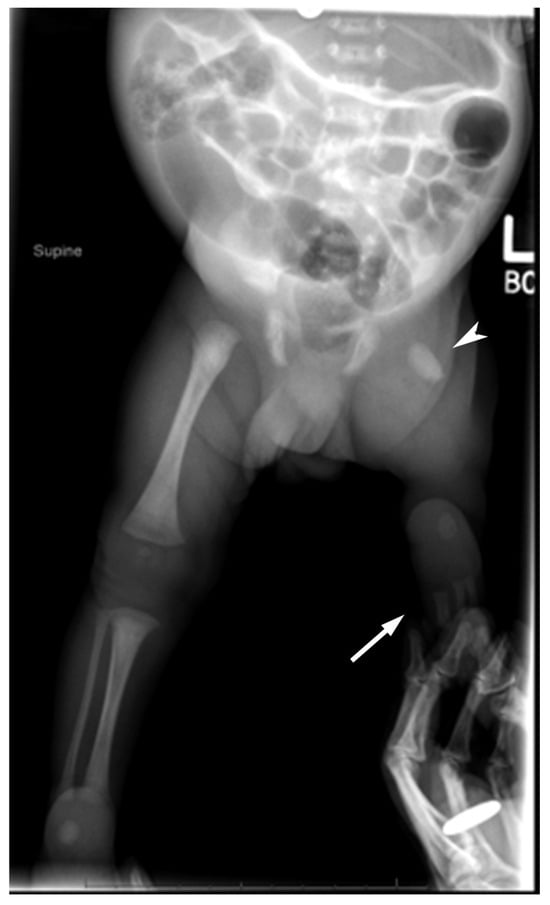

2.1. Case 1

2.2. Case 2

2.3. Case 3